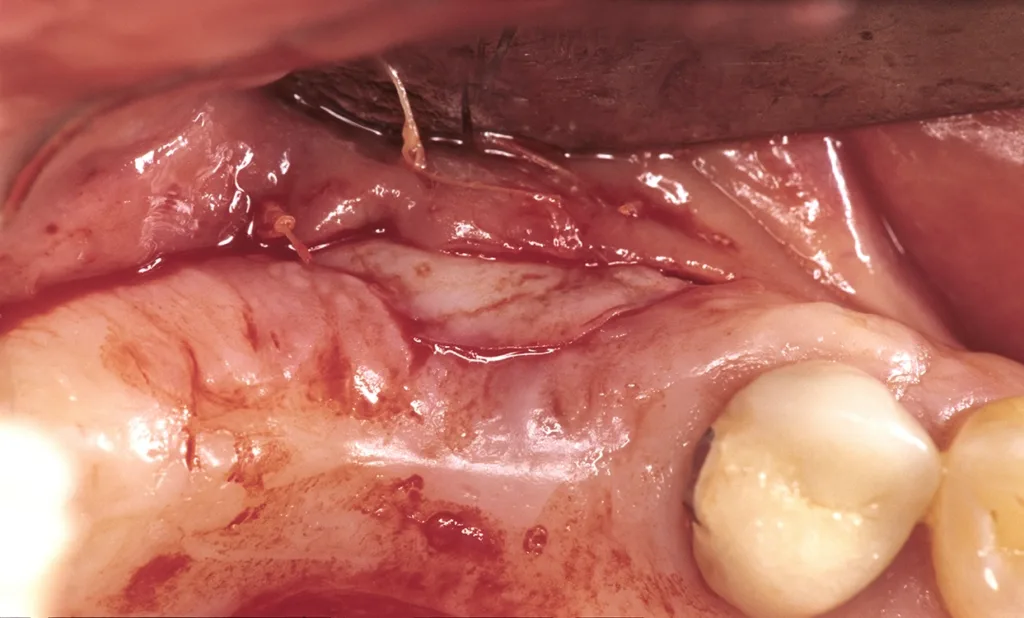

Daraus resultiert ein zweizeitiges Vorgehen mit (i) Entfernung prognostisch unsicherer Zähne, (ii) parodontaler Zieltherapie zur Sicherung des Restzahnbestandes, ergänzt durch (iii) mikrochirurgische Revision tiefer Resttaschen vor Implantation zum weiteren Entzündungsschutz (Abb. 3 und 4). Die Implantatplanung bleibt vorläufig. Ein definitiver Kostenvoranschlag wird erst nach funktioneller Entlastung und digitaler Beurteilung der Implantatknochenanatomie erstellt.

- Bei lateraler Augmentation ist eine Verbreiterung aufgrund der Lappenmobilisation zur Defektdeckung absehbar. In der Einheilungsphase vor Freilegung separater Behandlungstermin mit Vestibulumplastik und freier Schleimhauttransplantation (Gaumen) (Abb. 17 bis 19).